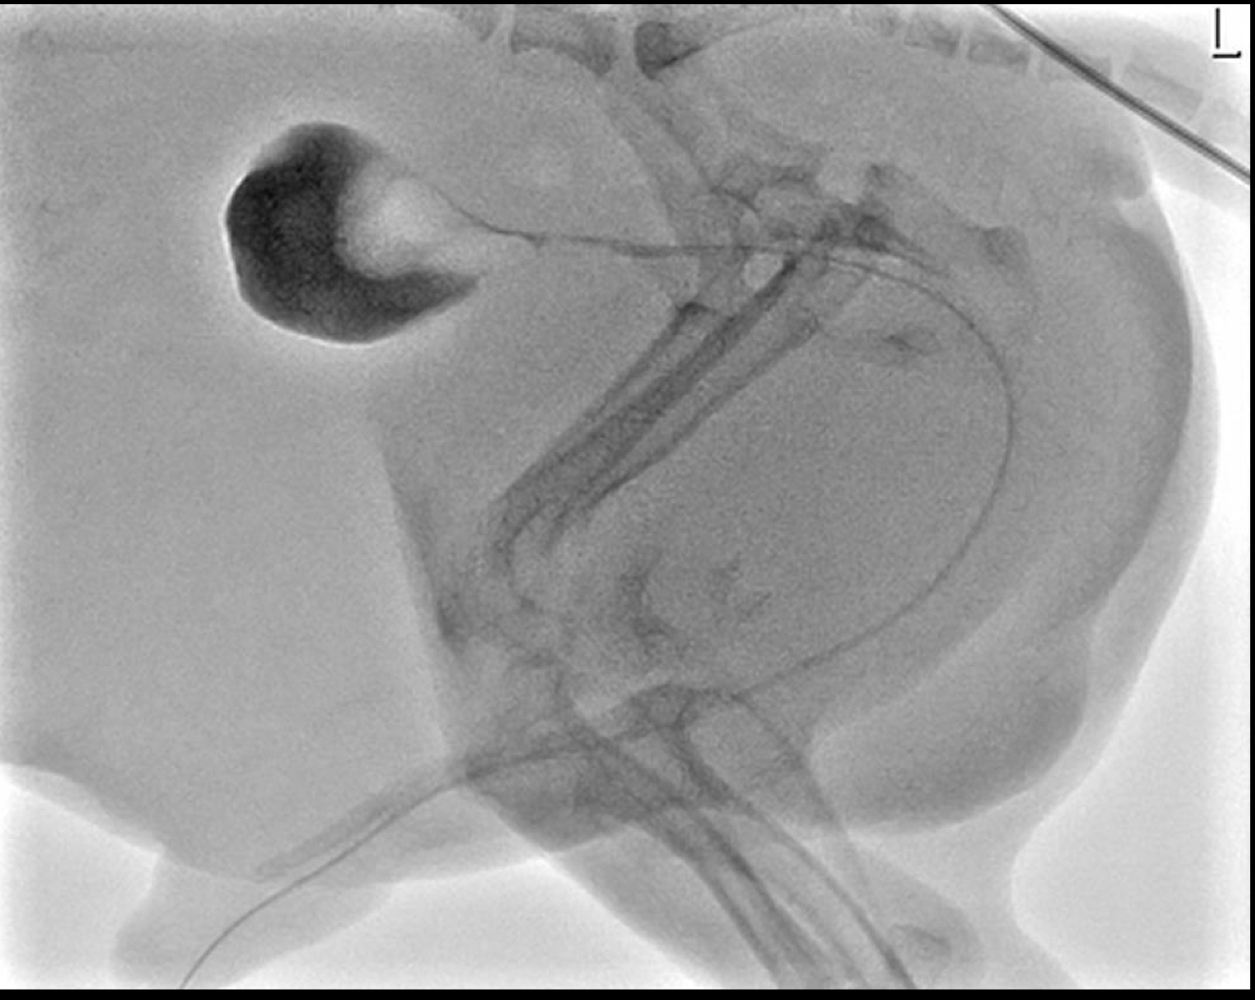

Feline fluoroscopic urethrogram:

broadly distended